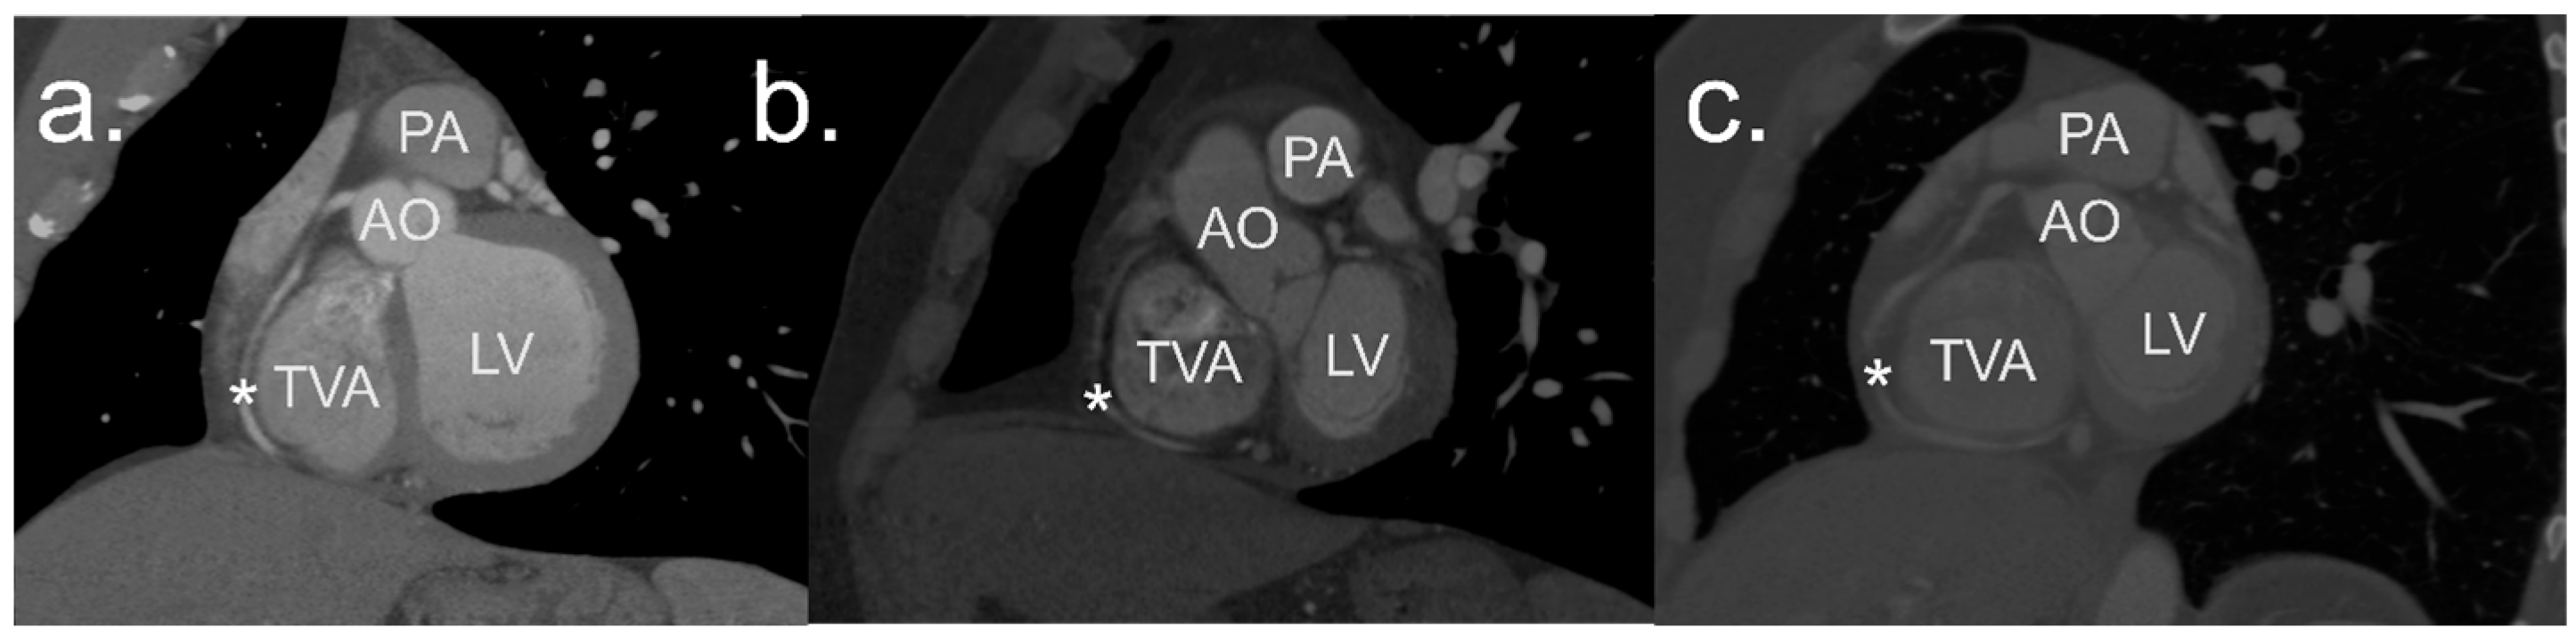

1.1. Anatomy of the Annulus of the Tricuspid Valve

1.2. Clinical Significance of the Region of the Tricuspid Valve Annulus

2.2. Image Processing and Analysis

2.3. Definitions

2.4. Measurements